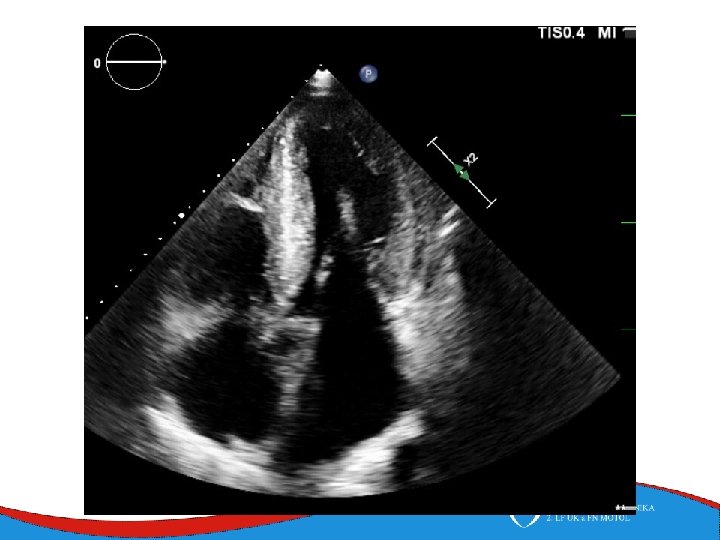

ECHO – anterior wall akinesis, LV EF 35%, mild mitral regurgitation, no dilation of right-sided chambers, no pericardial effusion